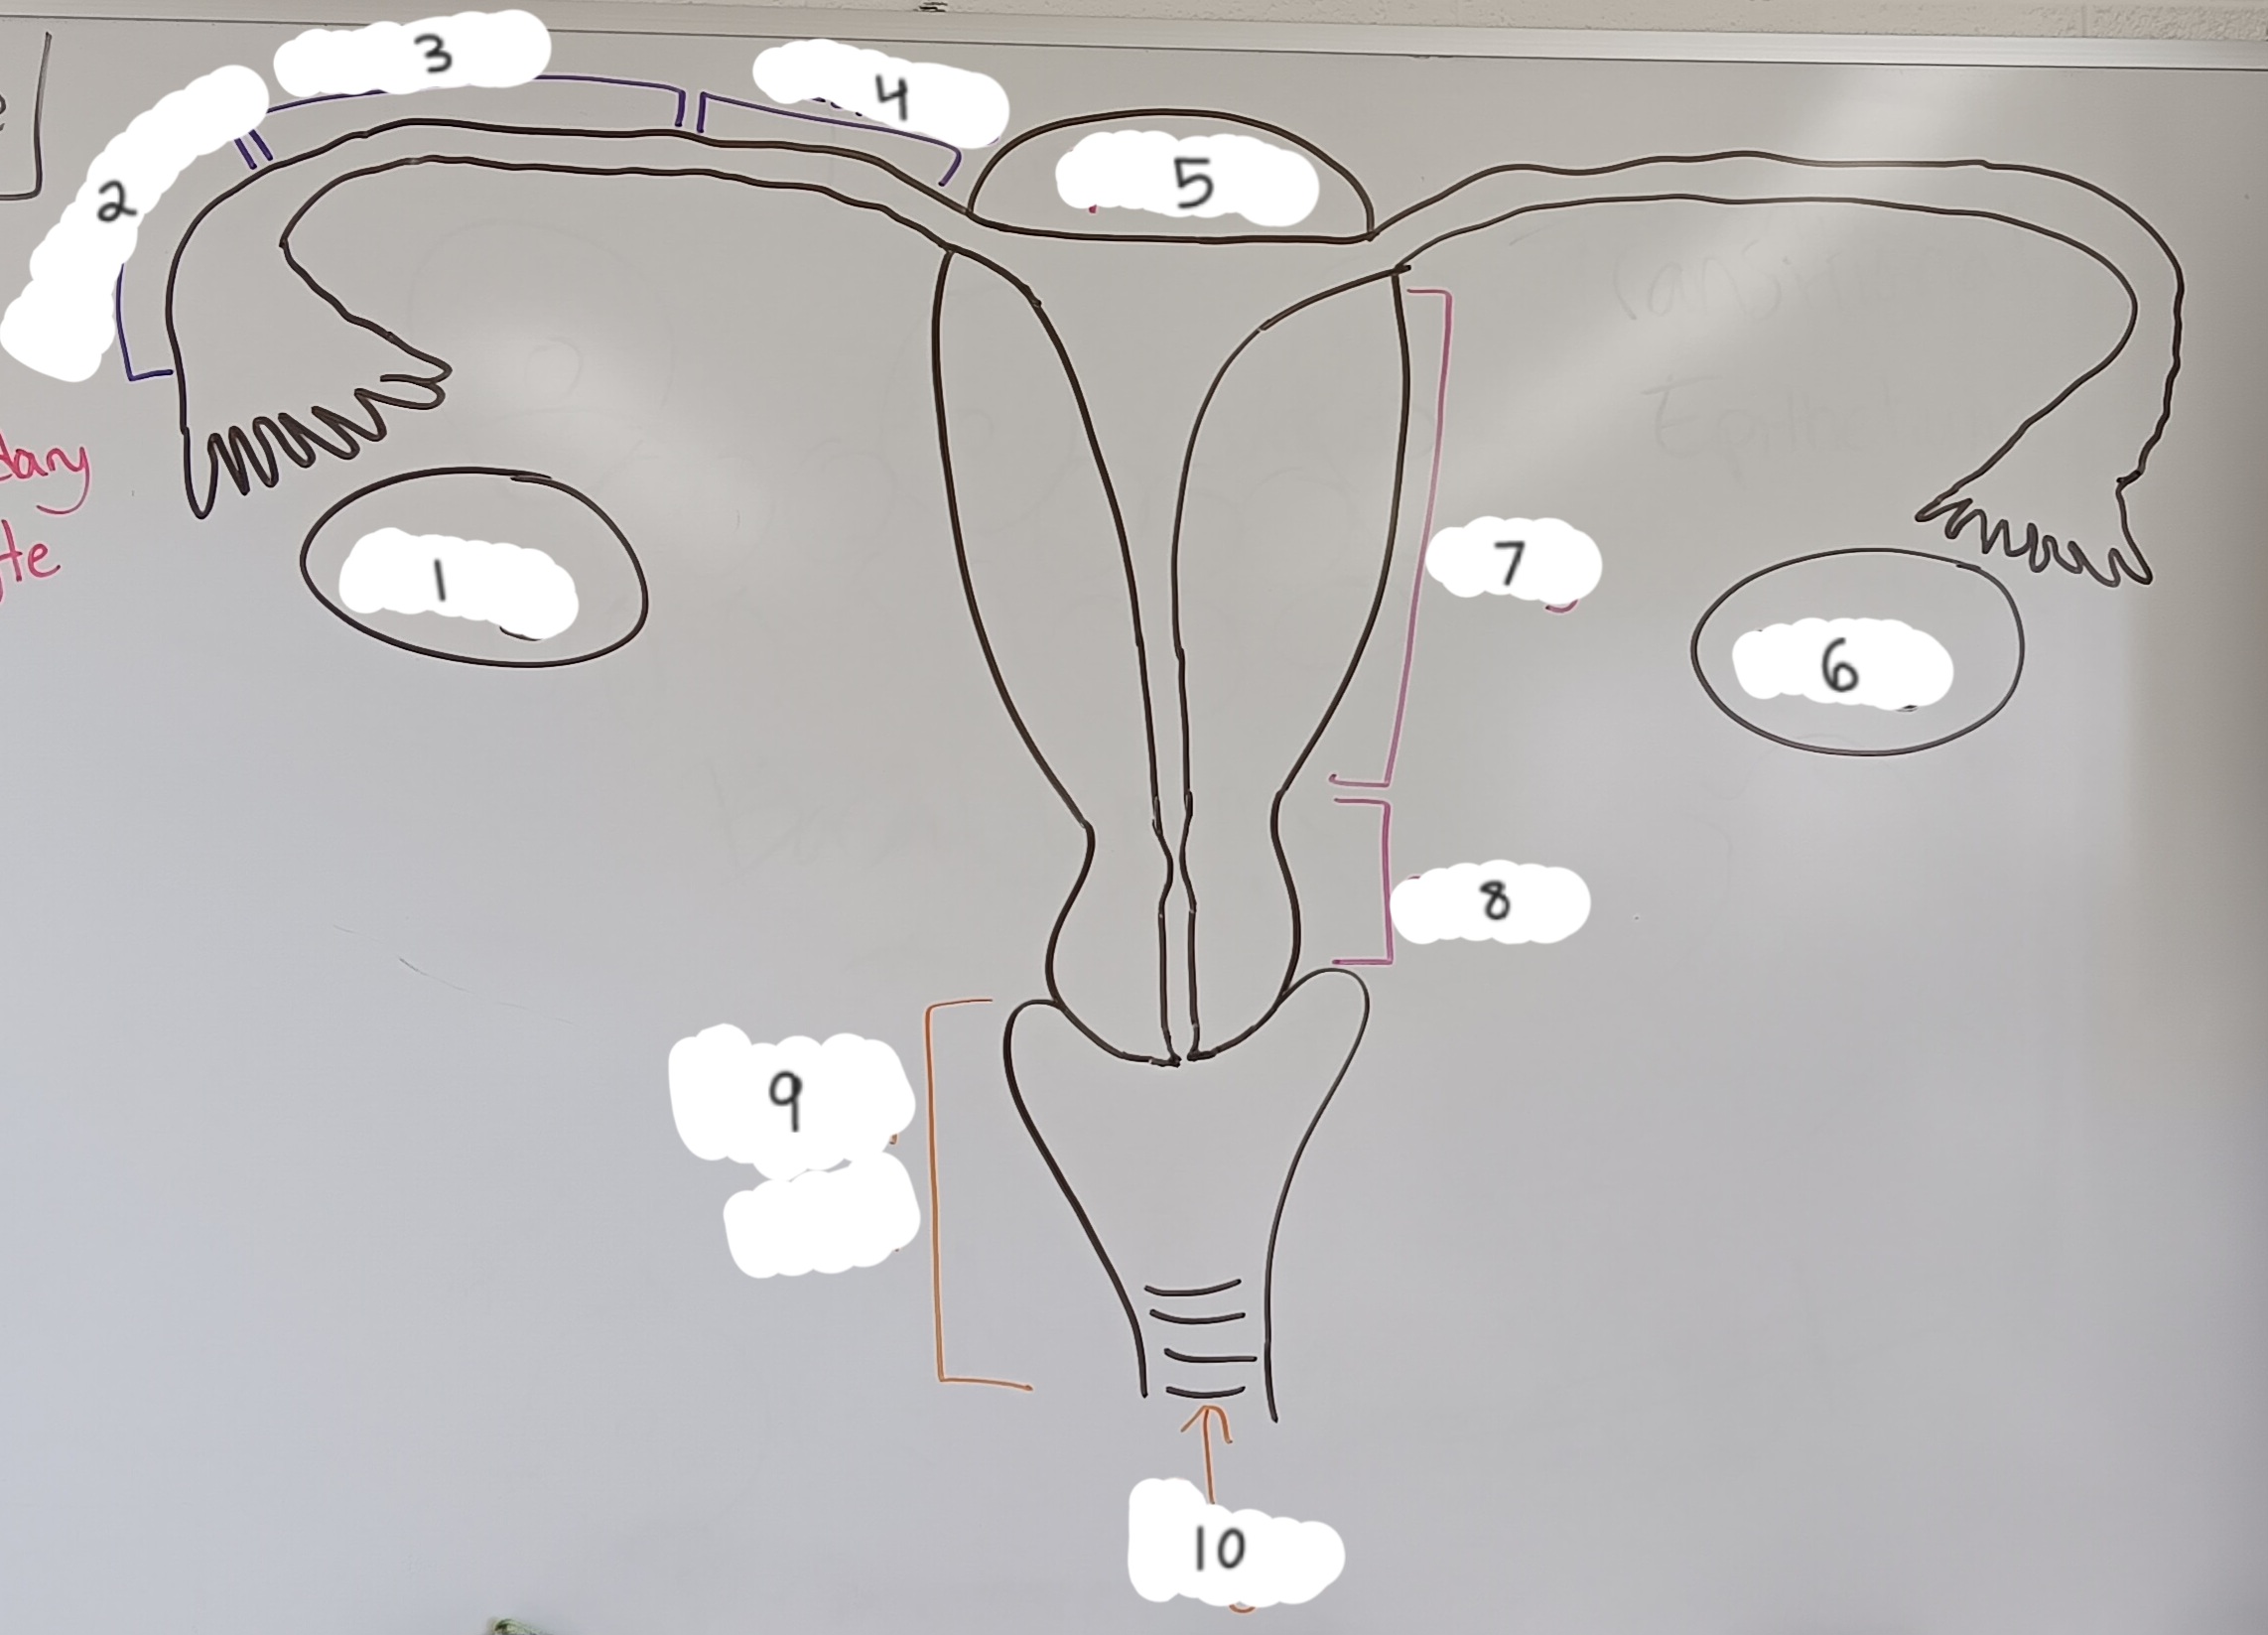

right ovary

1 (lt or rt)

infundibulum

2

ampulla

3

isthmus

4

fundus

5